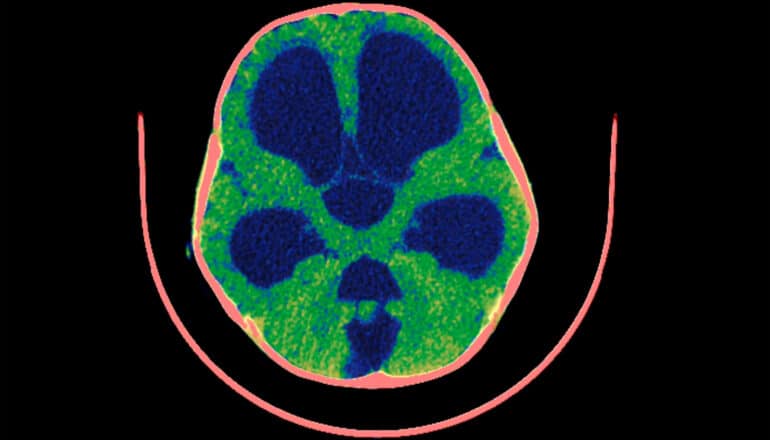

Many of the theories around this connection relate to smoking’s impact on the vascular and respiratory systems—essentially choking the flow of oxygen to the brain over decades of tobacco use. But the new study published in Science Advances points to the involvement of nicotine-triggered miscommunication.

The researchers found a previously unmapped route from the lungs to the mind through pulmonary neuroendocrine cells (PNECs). When exposed to nicotine, these cells release exosomes—tiny particles that transport cellular products and waste—that disrupt the iron balance in neurons, triggering symptoms often found in dementia patients.

“This iron [dysregulation] drives oxidative stress, mitochondrial dysfunction, and increased α-synuclein [protein] expression—hallmarks of neurodegenerative disease,” Chen says.

An iron imbalance in neurons can also wrongly trigger ferroptosis, a form of programmed cell death, in cells that weren’t supposed to die. Previous research has associated ferroptosis with both Alzheimer’s and Parkinson’s, but much more study is needed before any causal link can be claimed.